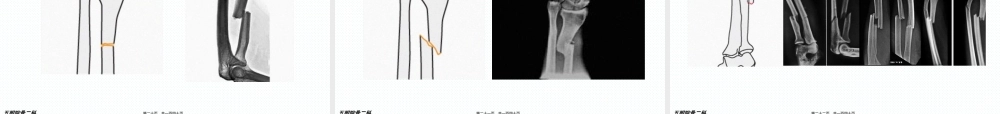

www.gukedoctor.com前臂(qiánbì)骨折五附院骨二科第一页,共一百四十页。五附院骨二科尺桡骨(ráogǔ)双骨折尺骨单骨折桡骨单骨折前臂远端骨折(shòukè)第二页,共一百四十页。五附院骨二科(tǐbiǎo)第三页,共一百四十页。五附院骨二科(tǐbiǎo)第四页,共一百四十页。五附院骨二科(qiánbì)第五页,共一百四十页。五附院骨二科第六页,共一百四十页。五附院骨二科(qiánbì)第七页,共一百四十页。五附院骨二科(qiánbì)第八页,共一百四十页。五附院骨二科(qiánbì)第九页,共一百四十页。五附院骨二科桡神经深支和后侧骨间神经:桡神经在肘窝外侧,肱骨外上髁前方,分浅、深两支桡神经深支发出肌支至桡侧腕长、短伸肌和旋后肌,然后(ránhòu)穿入旋后肌,在桡骨头下方5~7CM出穿出该肌,称为后侧骨间神经,走行与前臂肌后群浅、深两层之间分短支与长支(qiánbì)第十页,共一百四十页。五附院骨二科(qiánbì)第十一页,共一百四十页。五附院骨二科(qiánbì)第十二页,共一百四十页。五附院骨二科(qiánbì)第十三页,共一百四十页。五附院骨二科(qiánbì)第十四页,共一百四十页。五附院骨二科A型简单(jiǎndān)骨折(A1,A2,A3)B型锲型骨折(B1,B2,B3)C型复杂骨折(C1,C2,C3)(qiánbì)第十五页,共一百四十页。五附院骨二科A1.1斜型骨折(gǔzhé)第十六页,共一百四十页。五附院骨二科A1.2横型骨折(gǔzhé)第十七页,共一百四十页。五附院骨二科A1.3伴有桡骨头脱位(tuōwèi)(孟氏骨折)第十八页,共一百四十页。五附院骨二科A2.1斜型骨折(gǔzhé)第十九页,共一百四十页。五附院骨二科A2.2横型骨折(gǔzhé)第二十页,共一百四十页。五附院骨二科A2.3伴头下尺桡关节脱位(tuōwèi)(盖氏骨折)第二十一页,共一百四十页。五附院骨二科A3简单(jiǎndān)的双骨折第二十二页,共一百四十页。五附院骨二科B1.1完整(wánzhěng)锲型第二十三页,共一百四十页。五附院骨二科B1.2带有碎片(suìpiàn)的锲型骨折第二十四页,共一百四十页。五附院骨二科B1.3伴有桡骨头脱位(tuōwèi)(孟氏骨折)第二十五页,共一百四十页。五附院骨二科B2.1完整(wánzhěng)锲型第二十六页,共一百四十页。五附院骨二科B2.2碎片(suìpiàn)锲型第二十七页,共一百四十页。五附院骨二科B2.3伴有下尺桡关节(guānjié)脱位(盖氏骨折)第二十八页,共一百四十页。五附院骨二科B3.1尺骨锲型,桡骨简单(jiǎndān)骨折第二十九页,共一百四十页。五附院...